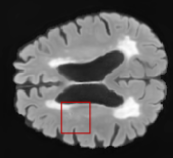

We evaluated our method in segmenting WMH from T1-w images using: a) Synthesized FLAIR images by treating the synthesis as a preprocessing step – we will refer to this method as offline synthesis; b) Synthesized FLAIR images using the proposed method, and c) without any synthesis – we will refer to this method as Unimodal. Baseline methods are illustrated in Figure 2

Table 2: Segmentation results for all proposed methods, each column represent a different slide in the image, blue areas are regions which were correctly labeled, false positives are shown in green, and false negatives in yellow

In order to better understand the above results, we visually analyzed the output segmentation performed for each method. Table 2 shows the results for three different slices (one slice per column). As illustrated, the proposed method is able to produce less false positives. It is also important to note that, unimodal segmentation is the one that produces more false positives, showing the advantage of using synthetic data. Regarding the nature of false positives, it can be easy to see in the third column a large number of false positives are on the border of periventricular lesions for the Unimodal method in comparison to the proposed method. Also from the first and second column, it can be observed that Unimodal tend to produce more small regions of false positives near to cortical areas. Removing such false positives requires additional post-processing steps, therefore, it is of value avoid this kind of over-segmentation. It can also be noted that synthesis methods tend to produce the same kind of false negatives, this may be due to the blurring effects in synthesized images since the information available during testing is limited – which otherwise is available from a FLAIR sequence.